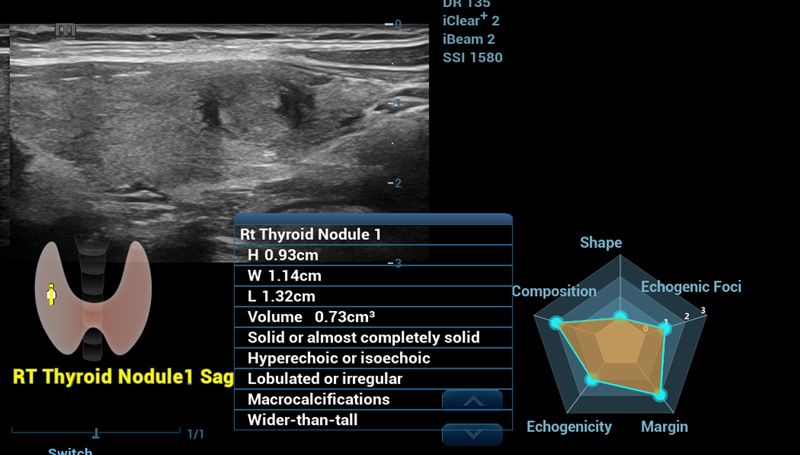

Smart Thyroid

Mais um plano para melhor vis?o

Smart Thyroid

O Smart Thyroid ûˋ uma ferramenta de anûÀlise e relatû°rio da tireoide para tornar a rotina clûÙnica de exames de tireoide mais precisa e produtiva.

Nû°dulo no Smart Thyroid